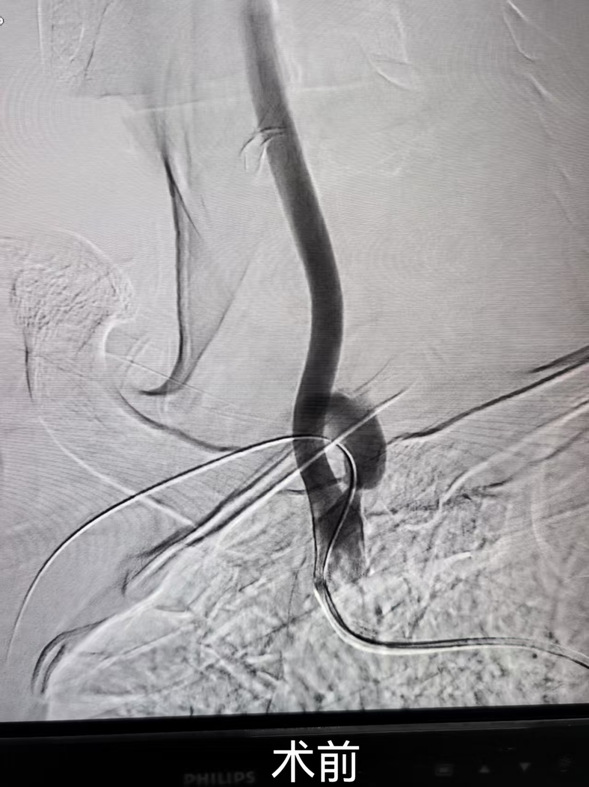

经过前期治疗,患者症状已有显著改善,但神经内六科医护团队并未放松警惕。继续为患者完善锁骨下动脉彩超及颈部CTA。结果显示:右侧锁骨下动脉盗血;右侧锁骨下动脉重度狭窄。医生们经缜密检查与分析决定,帮助患者解除潜在风险。

在综合考量患者的身体状况、病情进展及手术耐受程度等多方面因素后,任占军主任带领带领科室医生进行了术前讨论,决定为其实施锁骨下动脉支架置入术,力求消除隐患,让患者重获健康生活。